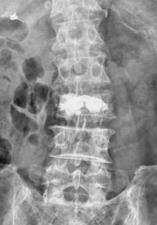

椎体形成術(VP、BKP、VBS)

対象となる疾患は、脊椎圧迫骨折や転移性脊椎腫瘍による病的骨折などです。原則、手術翌日より軟性もしくは硬性のコルセットを装着し、起立・歩行を開始します。単独で行うこともありますが、固定術と一緒に行うこともあります。単独で行う場合には、全身麻酔下に約5mmの皮切2ヶ所から細い筒を骨折椎体に挿入し、人工骨やセメントを注入して、骨折を人工的に接合します。

-

BKP (左)細い筒から骨折したせぼねに風船をしぼめた状態で設置して、ゆっくり風船を膨らませます。(中)膨れた風船が骨折した骨を復元します。(右)風船を取り出して空いたスペースにセメントを注入します。 -

VBS後 正面像 -

VBS後 側面像

BKPと同様に細い筒から骨折したせぼねに風船をしぼめた状態で設置して、ゆっくり風船を膨らませます。風船でステントを広げてスペースを作り、風船を取り出してステントとともにセメントを注入します。